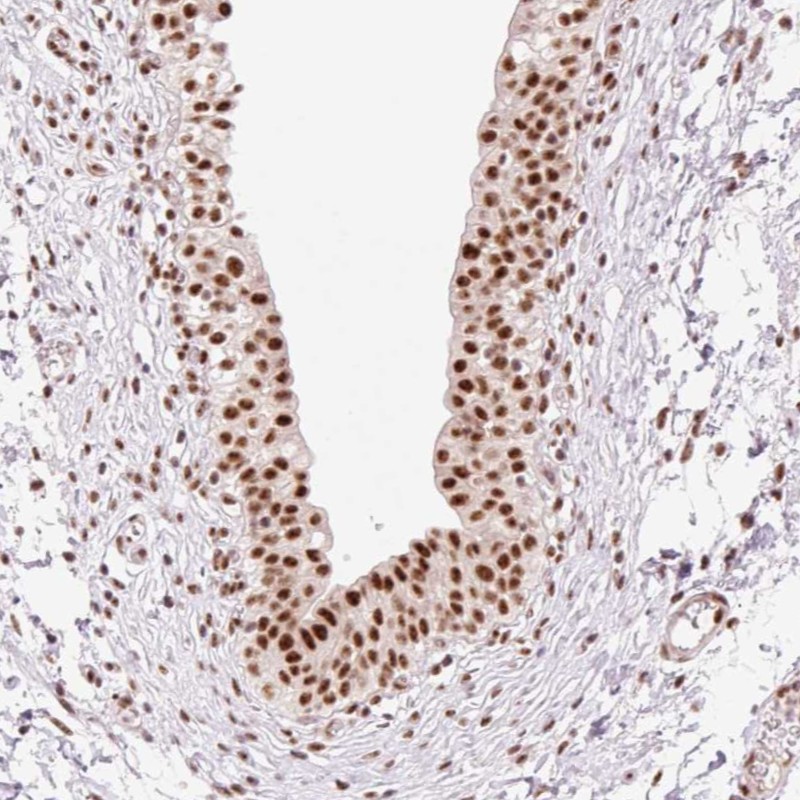

Immunohistochemical staining of human urinary bladder shows strong nuclear positivity in urothelial cells.